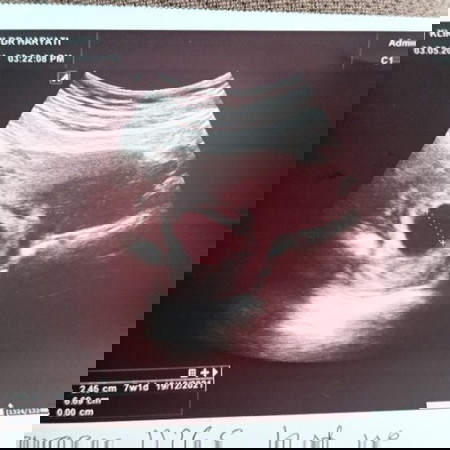

7minggu kantung sahaja

normal ke tak 7minggu nampak kantung jew. baby masih tak nampak lagi sedih lah😔

sama la cam sya smlm scan nmpak kantung je..doc ckp normal sbb 6 mnggu klu nak nmpk dlm 8 mnggu ke atas😊😊😊cuma jaga diri elok2..fkir yang positif jer.

Normal sis. Sama la. Mnggu 7 nmpk kantung je. Msuk mnggu 9,dah nmpak isi dlm tu. Fkir yg positif2 je..

selalu 7w nmpk samar2 je mase scan. normal ni. nt lg 2 minggu nmpk.